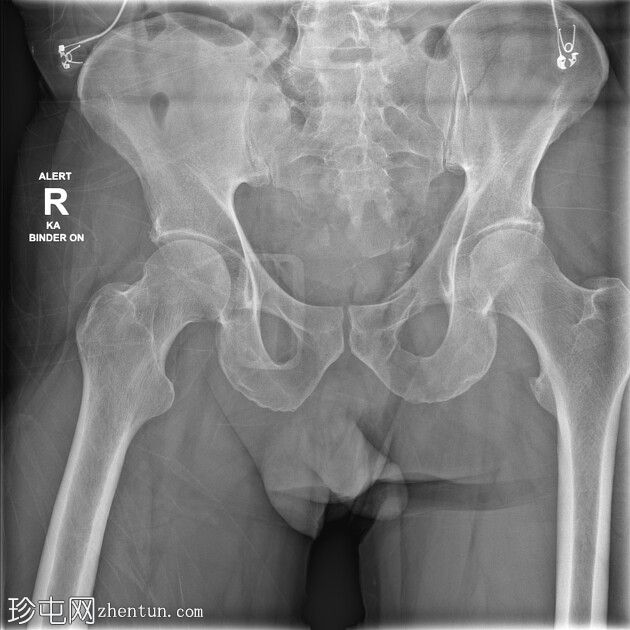

CT

右侧骶骨斜形粉碎性骨折伴移位导致广泛的腹膜后血肿,血肿延伸至主动脉分叉处。未见动脉显影或造影剂聚集,提示无活动性出血。骨折从第一骶椎椎体延伸至右侧骶骨翼,并累及右侧椎板。骶前间隙可见粉碎性骨折碎片。

左侧后髂骨轻度移位骨折,骨折线从髂嵴延伸至骶髂关节。骶髂关节对位正常。尾骨脱位并向左侧移位。盆底肌肉扭曲并向左侧移位,但其他方面看似完整。

左侧耻骨上下支粉碎性骨折。髋臼和耻骨联合未受累。